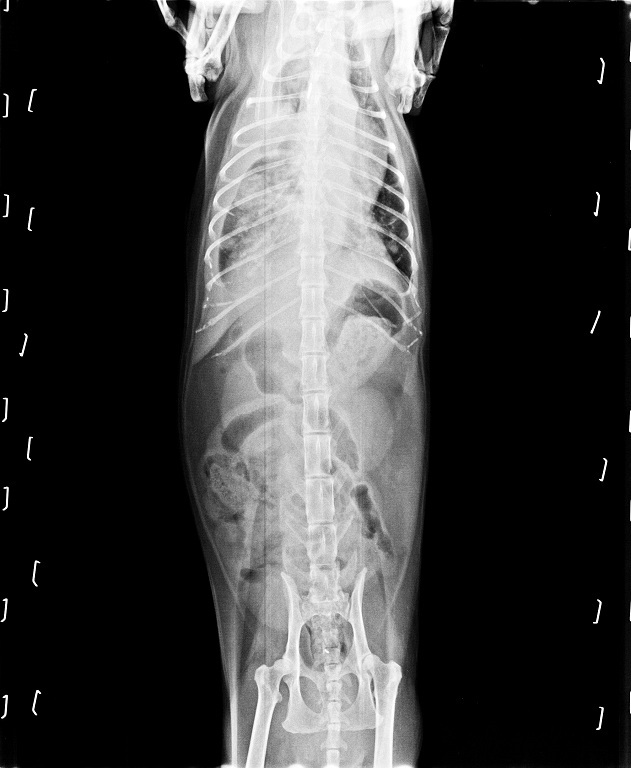

醫生在詳細檢查後,

發現波波胸腔內有腫瘤,

除此之外還有肺積水的問題,

是導致波波喘不過氣來的原因。